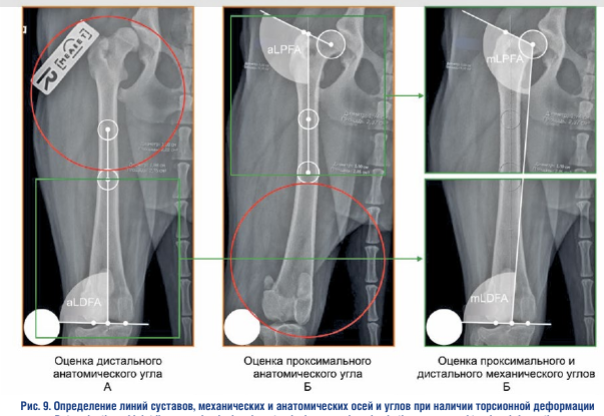

Определение линий суставов, механических и анатомических осей и углов при наличии торсионной деформации. При наличии торсионной деформации бедренной кости, невозможно получить рентгеновский снимок, на котором одновременно будут визуализироваться в правильном ортопедическом положении проксимальный и дистальный эпифизы.

Так, на рентгенограмме, выполненной с правильным положением дистального эпифиза бедренной кости, проксимальный эпифиз будет визуализироваться в «косом» положении, что можно оценить по ненадлежащей визуализации его анатомо-рентгенологических ориентиров. На такой рентгеновской проекции можно достоверно оценить дистальный анатомический угол, проксимальный анатомический угол, а проксимальный и дистальный механический углы оценивать нельзя.

Если необходимо оценить проксимальный анатомический угол, необходимо выполнить дополнительную рентгеновскую проекцию бедренной кости во фронтальной плоскости с правильным положением проксимального эпифиза, при этом дистальный эпифиз автоматически развернется в «косое» положение, что можно оценить по ненадлежащей визуализации его анатомо-рентгенологических ориентиров. На такой рентгеновской проекции можно достоверно оценить проксимальный анатомический угол, дистальный анатомический угол, а также проксимальный и дистальный механический углы оценивать нельзя.

Если необходимо оценить проксимальный и дистальный механические углы, необходимо провести «слияние» двух рентгенограмм, при котором проксимальный и дистальный суставные концы будут находиться в состоянии правильной ортопедической проекции. Условная граница соединения рентгенограмм должна обеспечивать наиболее точное сопоставление кортикальных слоев кости из всех возможных вариантов как по ширине, так и относительно вертикальной оси кости с сохранением общей длины кости. На таком совмещенном изображении двух рентгеновских проекций можно одновременно достоверно оценить проксимальный и дистальный анатомические углы, а также проксимальный и дистальный механические углы.